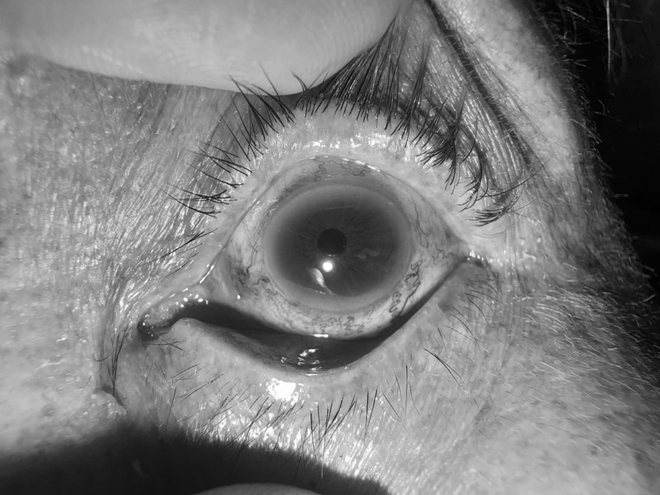

Đó là trường hợp của một cụ bà tên N.T.K, 80 tuổi (trú tại xã Phú Trạch, tỉnh Quảng Trị), vào Khoa Mắt, Bệnh viện Hữu nghị Việt Nam Cuba Đồng Hới, Quảng Trị khám với dấu hiệu mắt trái bị lồi to, đỏ mắt kéo dài. Ngoài ra, bà K. còn xuất hiện các triệu chứng đau nhức mắt và đặc biệt là tiếng ù tai theo nhịp mạch đập rì rầm liên tục trong đầu.

Hình ảnh mắt bệnh nhân trước (bên trái) và sau (bên phải) can thiệp.

Khi thăm khám cho bệnh nhân, các bác sĩ Khoa Mắt phát hiện mắt trái của cụ K. giảm thị lực, tăng nhãn áp, lồi mắt, giãn tĩnh mạch thượng củng mạc, phù nề kết mạc, hạn chế vận nhãn. Nghi ngờ bệnh nhân bị rò động mạch cảnh xoang hang trái, các bác sĩ đã chỉ định chụp X- Quang số hóa xóa nền (DSA) và có kết quả rò động mạch cảnh xoang hang bên trái.

Chỉ 24 giờ sau thủ thuật, tiếng ù tai trong đầu bệnh nhân hoàn toàn biến mất, tình trạng lồi mắt giảm rõ rệt, mắt hết đỏ và thị lực phục hồi tốt trong sự vui mừng của gia đình và đội ngũ y bác sĩ.